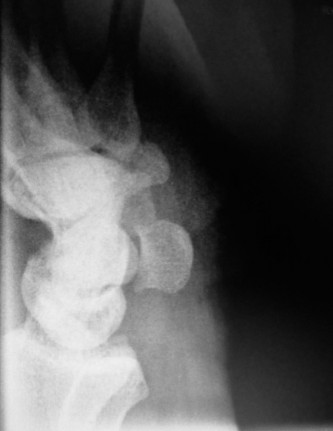

CASE 11 A patient presents to your clinic with ulnar-sided wrist pain. X-ray is…